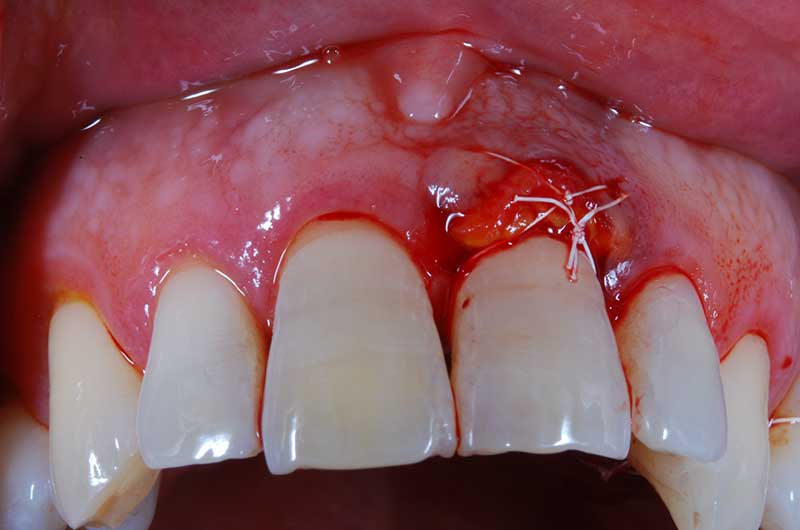

Lembo libero per correggere una recessione gengivale